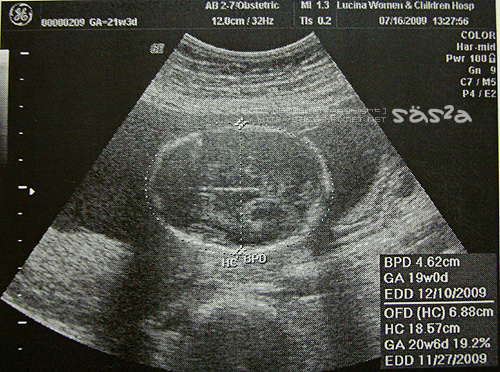

當然我們也看到傳說中的彩色影像,醫生介紹著臍帶血的流動,兩條呈現一個Y字型,紅色的血液正流動著,好神奇。最後唐氏症的檢查報告出爐啦!醫生說照一般產檢就可以了。我想...這是正常的意思嗎?柚子泥目前21W4D,體重345G,比起同周數的400G少上一些,醫生說在正常值內,還有很長的時間可以慢慢長,多吃點甜也可以。柚子泥一定知道媽咪不想要他太大隻,怕不好生XDDD